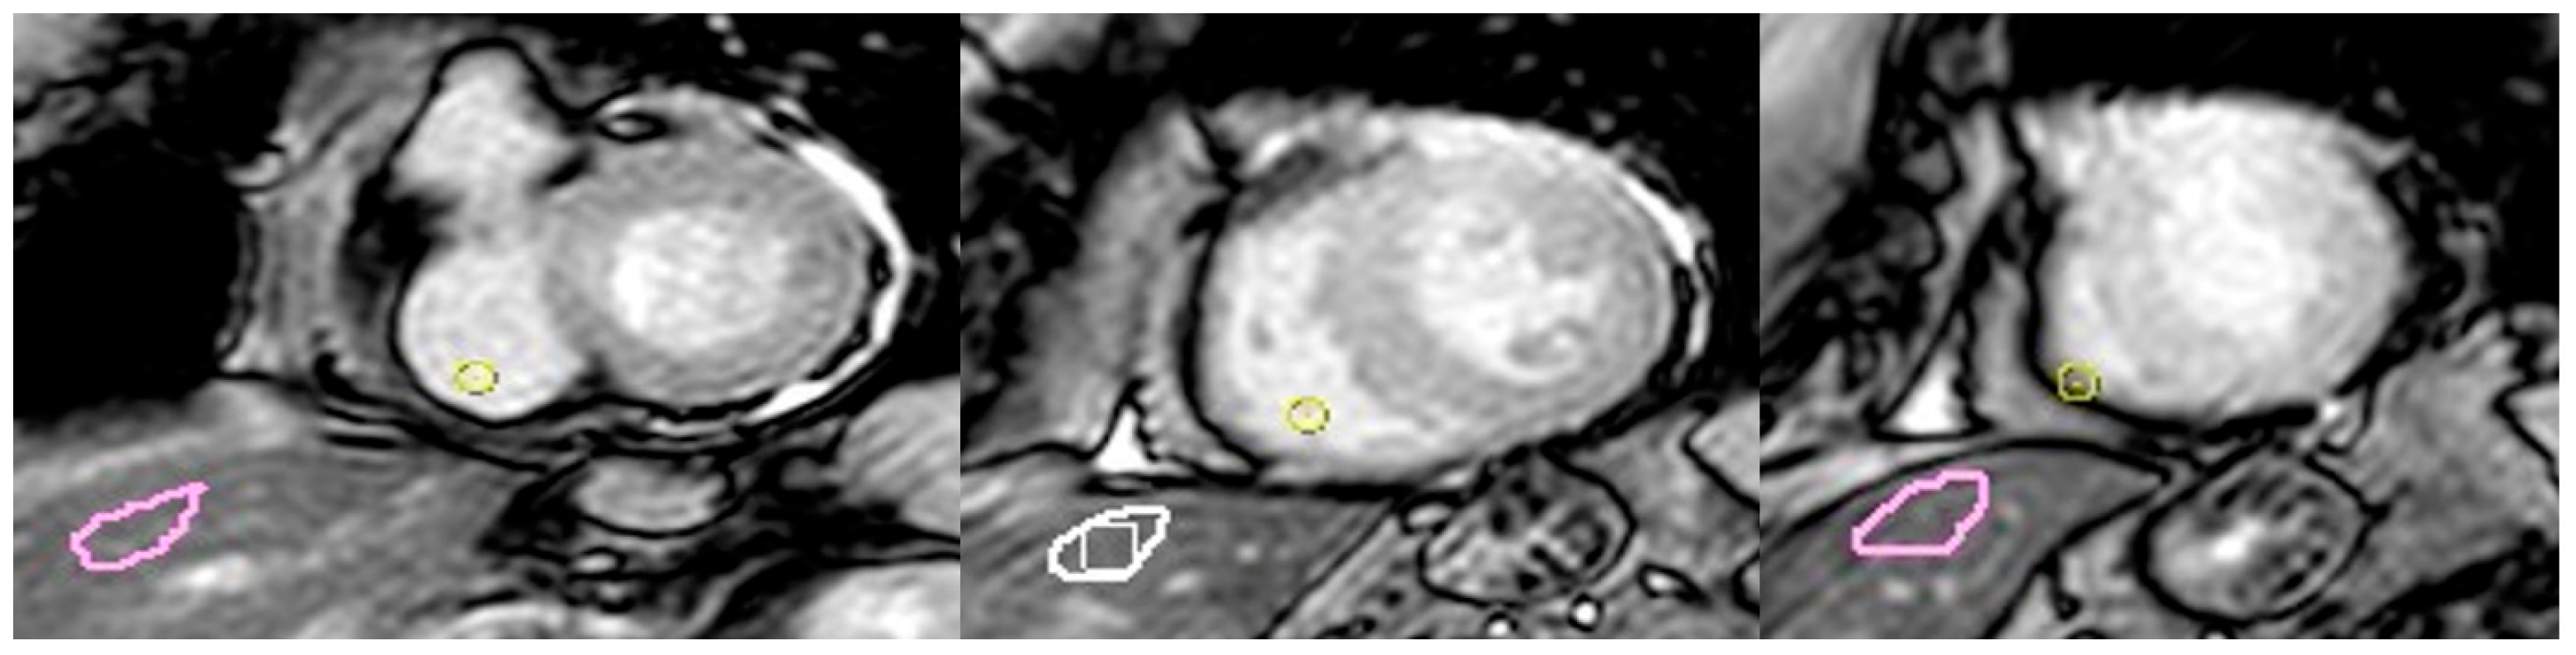

2.2. CMR Acquisition

2.3. CMR Image Post-Processing